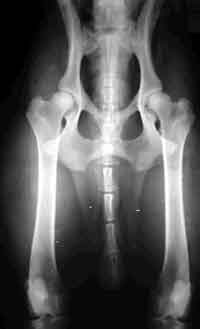

HD (Hüftgelenksdysplasie)

HD ist eine Fehlbildung der Hüftgelenke - das heißt Oberschenkelkopf und Gelenkpfanne passen nicht korrekt aufeinander. Diese Fehlbildung kann unterschiedlich ausgeprägt sein und tritt oft beidseitig auf.

Norberg Winkel

HD-Grade

Wir unterscheiden zwischen 5 verschiedenen Schweregraden der HD.

HD-frei - A

Das Gelenk ist absolut unauffällig und der Norbergwinkel beträgt 105 Grad oder mehr

HD-Verdacht/Grenzfall - B

Der Norbergwinkel beträgt 105 Grad oder mehr und die Gelenkpfanne und/oder der Schenkelkopf sind leicht ungleichmäßig oder aber Gelenkpfanne und/oder Schenkelkopf sind gleichmäßig, aber der Norbergwinkel beträgt weniger als 105 Grad

leichte HD -C

Norbergwinkel 100 Grad oder kleiner, ungleichmäßiger Oberschenkelkopf und Gelenkpfanne. Unter Umständen sind auch schon leichter arthrotischer Veränderungen zu bemerken.

mittlere HD - D

Norbergwinkel größer als 90 Grad und deutliche Ungleichmäßigkeiten von Oberschenkelkopf und Gelenkpfanne. Veränderungen des Pfannenrandes und/oder arthrotische Veränderungen sind zu erwarten oder schon vorhanden.

schwere HD - E

Norbergwinkel weniger ald 90 Grad, abgeflachter Pfannenrand, auffällige Veränderungen an Oberschenkelkopf und Gelenkpfanne. Deutliche arthrotische Veränderungen sind zu erwarten oder schon vorhanden.